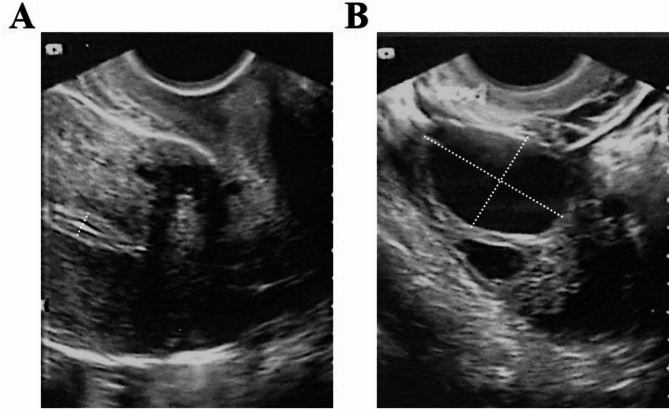

Case presentation: We report the case of a 29-year-old woman with severe IUA, RSA, and PCOS, who experienced three spontaneous abortions. Copy number variations (CNV's) detection of fetal villi from the last abortion indicated Turner syndrome. Hysteroscopic adhesiolysis (HA) had been performed twice previously. She subsequently underwent superovulation using an antagonist regimen, resulting in oocyte retrieval and cryopreservation of four transplantable blastocysts after genetic testing. After three rounds of HA, the uterine cavity shape returned to normal. She then received two cycles of Femoston and/or estradiol valerate therapy combined with oral low-dose aspirin, vaginal sildenafil, pelvic floor electrical stimulation, and uterine perfusion platelet-rich plasma (PRP); however, the frozen embryo transfer (FET) was canceled as the EMT remained 4.9 mm and 3.9 mm. After three additional HA procedures and one hysteroscopy, the uterine cavity returned to normal. She then received tamoxifen (TAM) with estradiol valerate and human menopausal gonadotropin (HMG), achieving an EMT of 7.5 mm after ovulation. Ultimately, the frozen transfer of a 4BB blastocyst resulted in the birth of a healthy baby boy.